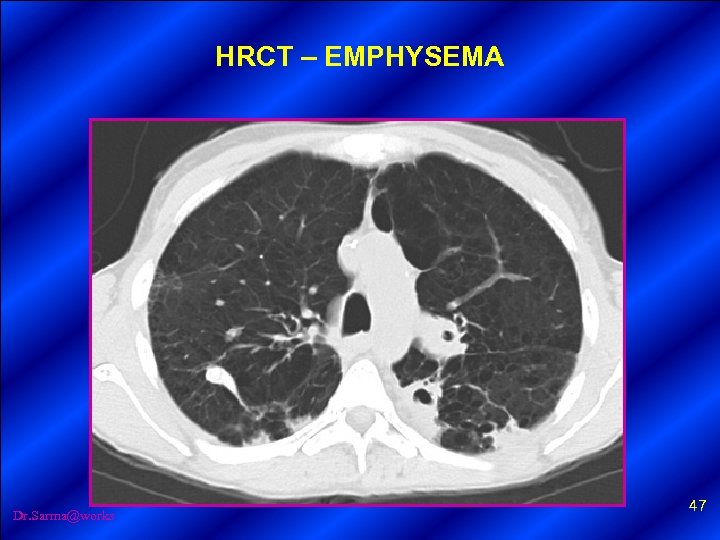

HRCT – EMPHYSEMA Dr. Sarma@works 46

HRCT – EMPHYSEMA Dr. Sarma@works 47